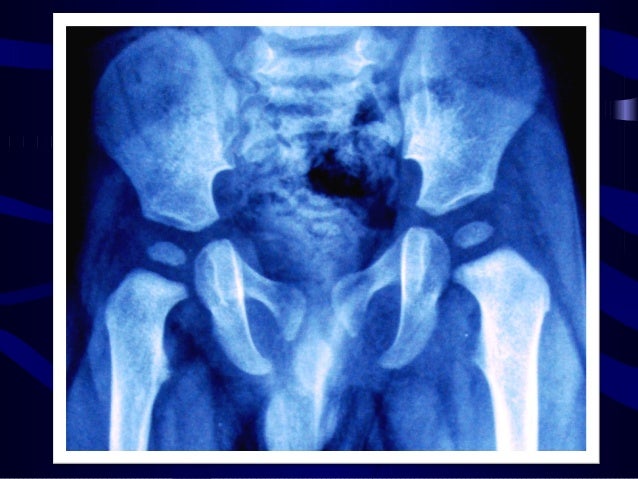

Souvent, la luxation de l’articulation de la hanche se reconnaît déjà à la mauvaise position de la jambe : Hanche labrum. En cas de luxation postérieure, la jambe est tournée vers l’intérieur, alors qu’en cas de luxation antérieure, elle est plus souvent tournée vers l’extérieur. Le diagnostic est confirmé par des radiographies du bassin.